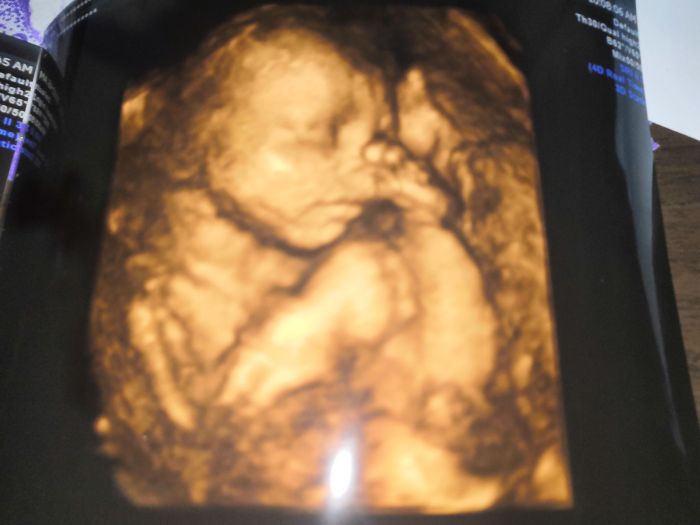

Jinak byly jsme na 4D ultrazvuku máme potvrzenou holčičku.. Tak snad je to tak ? přikládám i foto. Jen se moc nechtěla ukazovat obličejik si zakryvala packama...